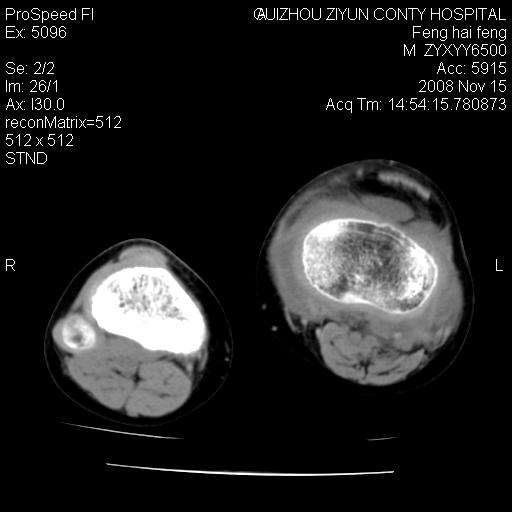

标题: CT16656:M 14Y 左膝关节肿胀一年余。其余病史不详。 [打印本页]

标题: CT16656:M 14Y 左膝关节肿胀一年余。其余病史不详。

考虑左侧髌骨结核;左膝关节滑膜肿胀、增厚,关节囊积液。

左膝滑膜型关节结核可能性大!支持!滑膜型关节结核主要ct表现:关节囊肿胀,积液,关节面见小破坏灶,并见点状死骨!

左膝滑膜型关节结核可能性大!支持!滑膜型关节结核主要ct表现:关节囊肿胀,积液,关节面见小破坏灶,并见点状死骨

好大的左腿!考虑左侧髌骨结核,左膝关节滑膜肿胀、增厚,关节囊积液。

左侧髌骨结核;左膝关节滑膜肿胀、增厚,关节囊积液